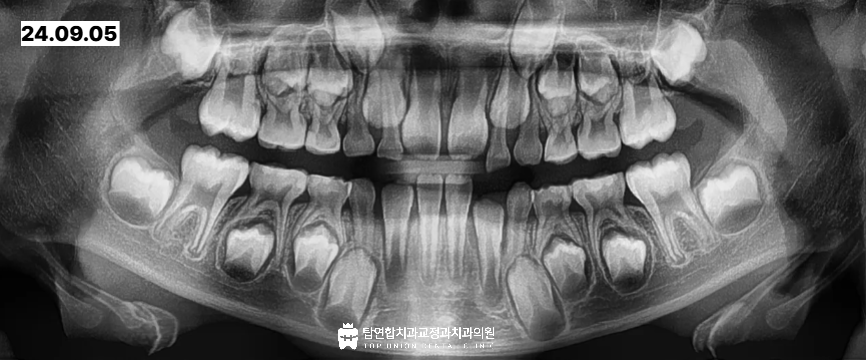

이번 증례는 7세 남아로

전체 x-ray를 통해서 전체적인 상태를 확인해 보았습니다.

아래 앞니에 통증을 느낀 것과는 별개로

아래 앞니에서 염증 등의 소견은 발견되지 않았고

유치열과 혼합치열이 공존하는 시기로

성장 조절에 매우 유리한 시점이었습니다.

다른 병원에서는 “조금 더 지켜보자”는 의견을 받았지만

본원에서는 치성 반대교합으로 판단되어

장치를 통한 조기 개입을 결정하였습니다.